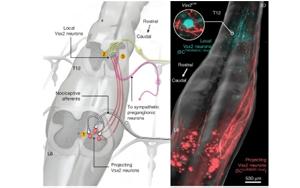

揭示自主神經(jīng)反射異常(AD)的神經(jīng)元架構(gòu):脊髓損傷后惡性高血壓發(fā)作的機制與神經(jīng)調(diào)控治療新策略

本研究首次系統(tǒng)性揭示了脊髓損傷(SCI)后誘發(fā)自主神經(jīng)反射異常(AD)的完整神經(jīng)元回路機制,發(fā)現(xiàn)Vsx2ON神經(jīng)元群在胸腰段脊髓中的核心樞紐作用。通過硬膜外電刺激(EES)靶向血流動力學熱點可重構(gòu)競爭性神經(jīng)回路,顯著逆轉(zhuǎn)小鼠、大鼠及人類AD癥狀。該發(fā)現(xiàn)為開發(fā)基于神經(jīng)回路的精準治療方案提供了理論依據(jù)。